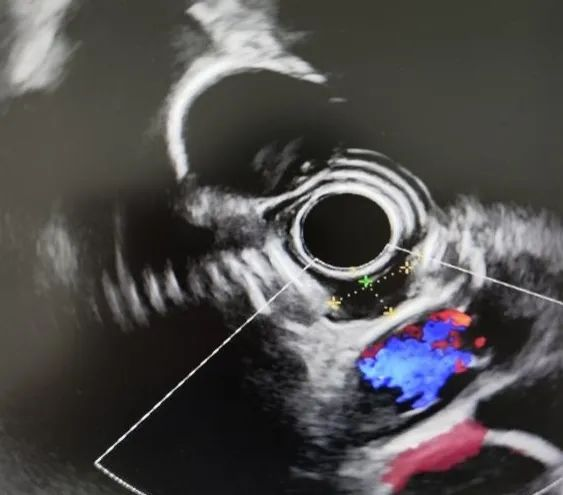

53岁的陈先生在我院行胃镜检查发现食管有一黏膜下肿物,超声内镜检查提示肿物起源食管固有层,消化内科李捷壮主任与省医派驻专家郑中文副主任带领内镜微创团队讨论,分析患者的瘤体位置特殊,长在食管中段,操作空间狭小,如果直接内镜下挖除,需要破坏肿物部位的黏膜层、黏膜下层甚至肌层,创面深而且大,导致术后愈合慢、瘢痕狭窄、食管穿孔等风险增加。

▲超声内镜下可见食管肿物起源食管固有层